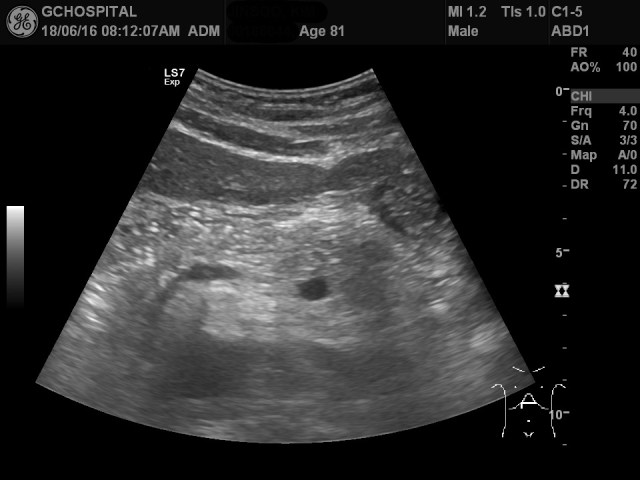

그런데, 췌장의 모양이 좀 이상합니다. 췌장의 머리와 몸통 모양이 잘 그려지지 않고, splenic vein 및 portal vein의 모양이 좌우가 뒤바뀌어 있습니다.

췌장의 위쪽에 있을 간 좌엽의 형태도 이상합니다. 간 좌엽에서 보여야 하는 좌측 간문맥이 정상적인 모양이 아닙니다.

쓸개도 처음에는 찾지 못했는데, 나중에 간의 거의 왼쪽 끝부분에서 발견할 수 있었습니다.